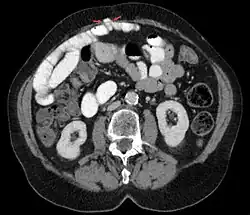

Nach dem Ort ihres Auftretens werden innere und äußere Hernien unterschieden. Ist die Hernie von außen zu erkennen oder führt die Bruchpforte vom Körperinneren in Richtung Haut, spricht man von einer äußeren Hernie. Liegt die Hernie innerhalb des Rumpfes (z. B. vom Bauch in den Brustkorb gerichtet) und kann deshalb nicht ohne Hilfsmittel erkannt werden, dann handelt es sich um eine innere Hernie.

Innere Hernien

Eine Hernie durch einen angeborenen Mesenterialdefekt ist eine seltene Ursache für einen Darmverschluss. Obwohl sie als „angeboren“ bezeichnet wird, werden die meisten Patienten mit einer Mesenterialhernie erst im Erwachsenenalter mit Symptomen vorstellig.[4]